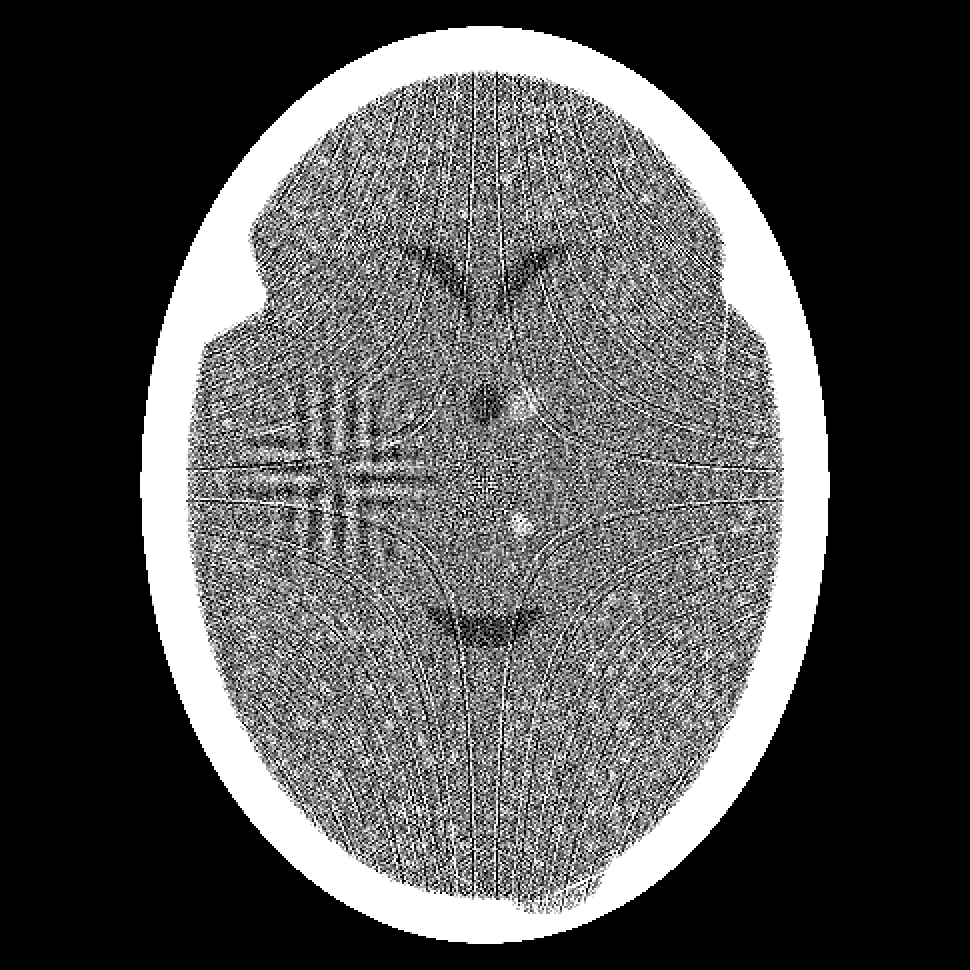

Figure 7: Results of the Shearlet-Based Superiorized Version of ART (left column) and the Modified Split Bregman Algorithm (right column) after the third (top row) and the tenth (bottom row) iteration from 720 projections.

We compared the performance of the Shearlet-Based Superiorized Version of ART with that of the Modified Split Bregman Algorithm on the projection data used in Subsection 4.1; the relative errors are reported in Fig. 6. In Fig. 7 we show the results of the two approaches after the third and the tenth iteration.